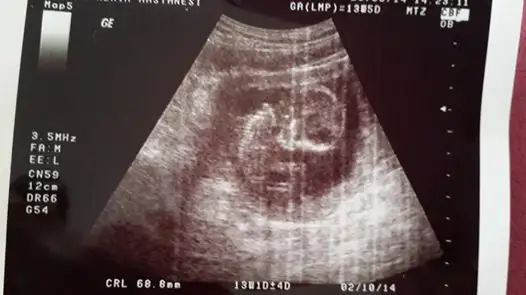

selam kızlar daha once burada usg goruntulerını paylasmıstım :) net sonucu yazayım dedım,erkek..

ya kızlar benim iki hafata önceki ultrasonum var belli midir? dr erkek muhtemelen dedi ama kesin demedi. yeni ultrasonu ekleyemedim bir türlü ışık patlaması oluyor. çocuğun kafası kocaman görüyodu korktum ya siiznkilerde de öyle oldu mu? kötü bişey olsa dr söylerdi dimi? ya da ultrasn eski diye mi öyle çıktı?

Eki Görüntüle 1016535

Eki Görüntüle 1016536 Eki Görüntüle 1016536